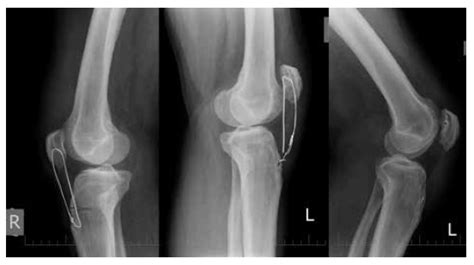

Medzi hlavné klinické prejavy patrí krívanie rôznej intenzity jednej alebo oboch predných končatín, hlavne po odpočinku a pri vstávaní, ako aj po dlhšej únavnej chôdzi, alebo po venčení. Pohyb môže byť po odpočinku tuhý alebo strnulý. Pes sa postaví a po krátkom čase krívanie rozchodí, a tak problémy s chôdzou majiteľ nemusí spozorovať. Diagnostika DLK prebieha röntgenologicky tzn. RTG vyšetrením vykonanom v celkovej anestéze na oficiálne schválenom RTG pracovisku, prípadne na CT (computed tomography). U nás zvyčajne spočíva v zhotovení RTG snímok lakťa ideálne z 2 projekcií (bočnej a predo-zadnej s 15°pronáciou).

Stupeň DLK sa medzinárodne označuje ako ED (elbow dysplasia) a interpretuje sa podľa IEWG (International Elbow Working Group) a FCI v štvorstupňovej škále od 0 do 3, hlavne v závislosti od výskytu osteofytov. Vyhodnotenie býva udávané dvoma číslicami ako výsledok stupňa pravého a ľavého lakťa: príklad DLK, alebo medzinárodne ED: 0/0.